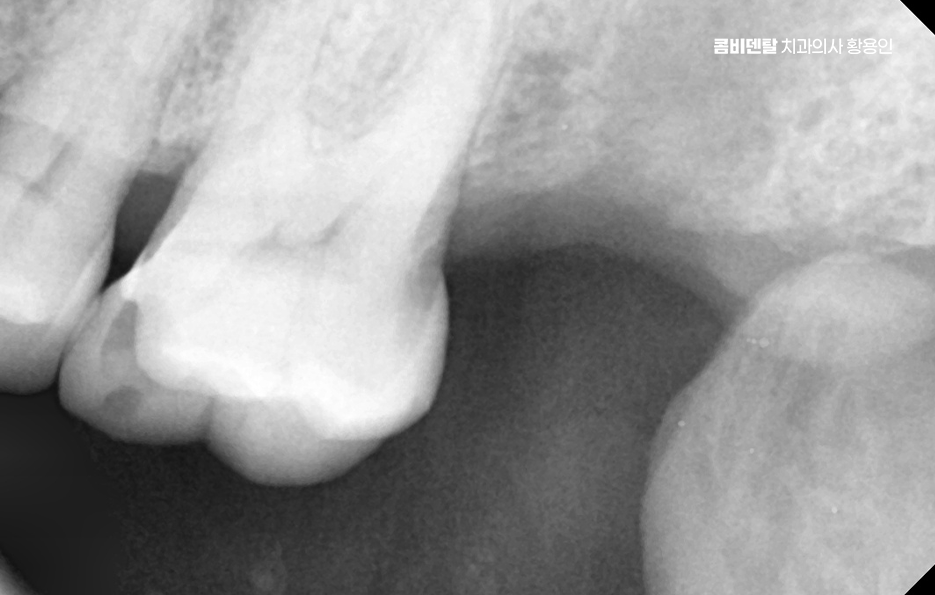

더 심각한 건 치열 전체가 무너지는 것으로 어금니가 빠지고 그 자리를 비워 두면, 위에 맞물리는 치아가 점점 내려오거나, 옆 치아가 쓰러져 들어가며 이렇게 정출된 치아는 다시 제자리로 돌아오지 않기 때문에, 나중에 임플란트를 하려고 해도 공간이 맞지 않아서 교정치료를 먼저 해야 할 수도 있었어요.

그래서 이런 문제들을 막기 위해서라도 임플란트는 어금니 상실 후 중요한 치료 옵션으로서 임플란트는 빠진 치아의 뿌리 역할까지 해주기 때문에, 단순히 공간을 채우는 게 아니라 턱뼈에 자극을 줘서 뼈 흡수를 막아주고, 위아래 치아가 정상적으로 맞물릴 수 있게 해주며 다른 보철 방식과 비교해도 장기적인 안정성과 기능 회복 면에서 유리한 거예요.

임플란트를 빨리 하는 게 좋은 이유는, 시간이 지나면서 턱뼈가 점점 흡수돼버리면 임플란트를 심을 뼈 자체가 부족해지는 상황이 생기기 때문이며 이때는 뼈이식이나 상악동 거상술 같은 추가 수술이 필요하게 되고, 치료 기간도 길어지고, 비용도 많이 올라가기 때문에 어금니가 빠졌다고 방치하는 시간만큼 치료는 더 복잡해질 수 있다는 점에서 어금니 없으면 얼굴 발음 및 오늘 알아본 것처럼 다양한 문제로 이어질 수 있음을 잘 이해하여 빠르고 나에게 맞는 치료 계획을 세우시고 장기적으로는 수명 유지까지 잘 고려하여 치료 계획을 잘 세워보시길 바라고 있어요